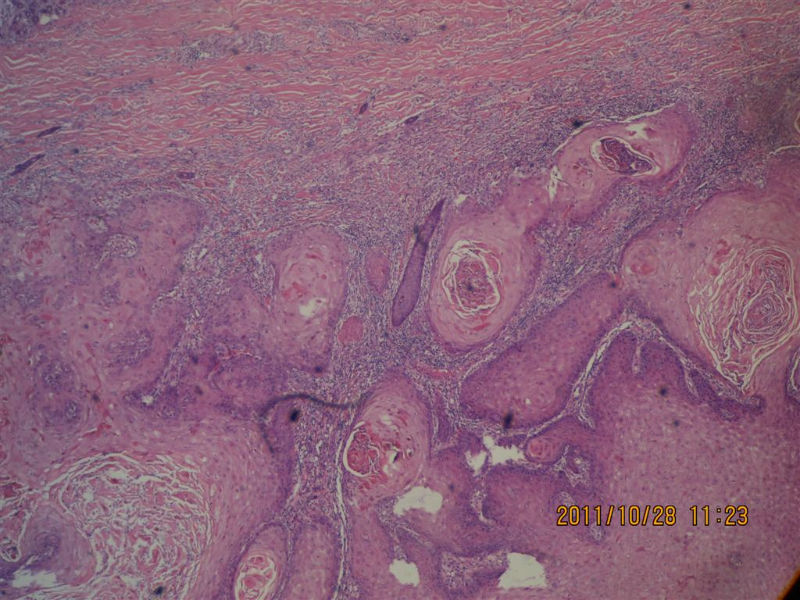

女性,71岁,右前臂肿物。角化棘皮瘤还是高分化鳞癌?

• 女性,71岁,右前臂肿物。角化棘皮瘤还是高分化鳞癌?图2

图2

不知道肿物的生长速度怎样?活动度?低倍看火盆样外观、唇样边缘,底部较平整,无明显突破。更趋向于角化角化棘皮瘤。

低倍镜见表皮呈火山口样,内充满角质团块,周边上皮增生呈衣领样,底部表皮增生呈假上皮瘤样,上皮角不规则延伸至真皮,真皮大量炎细胞浸润.

低倍镜下看符合角化棘皮瘤